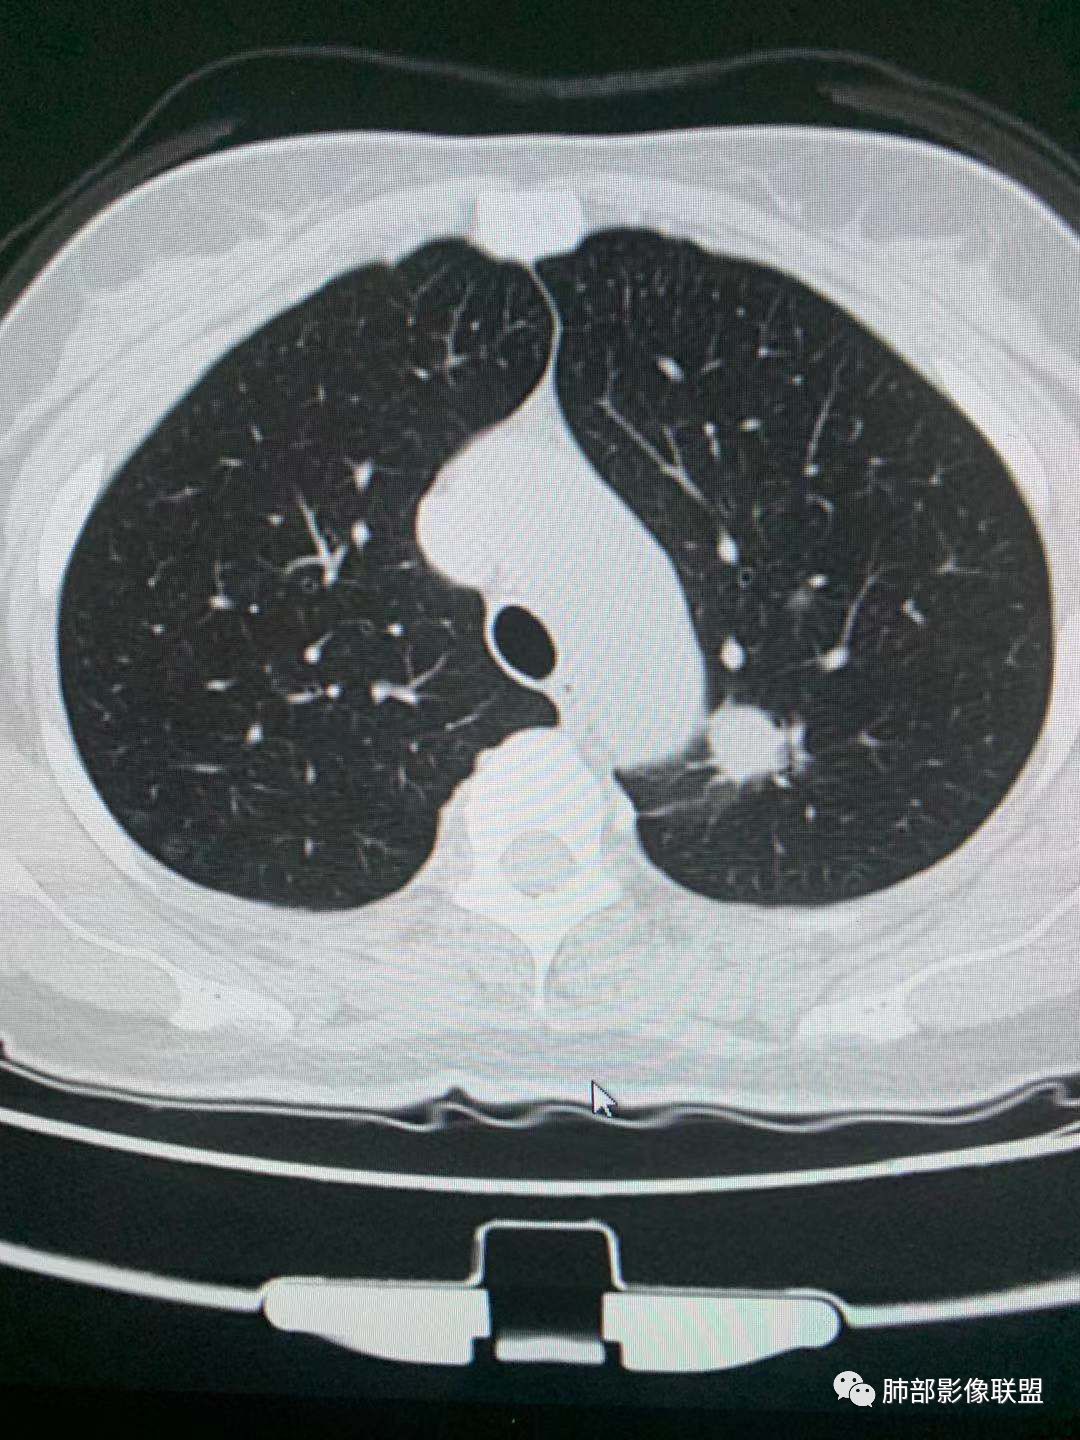

二、看第二个结节

1、密度?

2、边界?

3、收缩力?

4、血管?

5、大小、内部结构、CT值

金豆

纯磨玻璃 边界清

小兜

纯磨玻璃,能画出轮廓,但是感觉边缘又比较模糊,是层厚原因吗,收缩力弱,血管进入

心灵鸡汤

与左肺上叶纵隔旁pGGN

南边

三、看看这一个

1、密度:PGGN?MGGN?

lmg

这个密度要高一些,混合磨玻璃结节

MGGN,比上面两个密度高

这个结节中间密度稍高一些 不像纯的

都认为mggn,都觉得密度高了?

磨玻璃成分比例≥10%,<90%,为mGGN

<10%,为pGGN,≥90%为实性GGN

Ao..葉偲雨!

这个考虑Pggn

有一条血管进入

而且增粗了

密度确实周围稍低,中央偏高一些

边界清

支持原位?微浸润